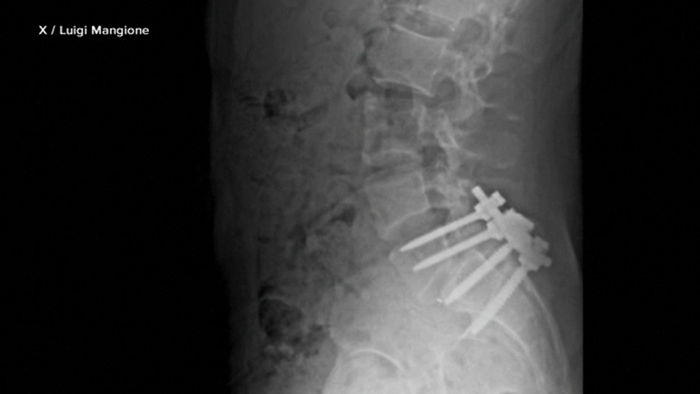

توجد في واجهة الحساب صورة أشعة لشريحة مسامير مثبتة على عمود فقري يُعتقد أنها تعود له